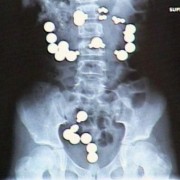

Батерии